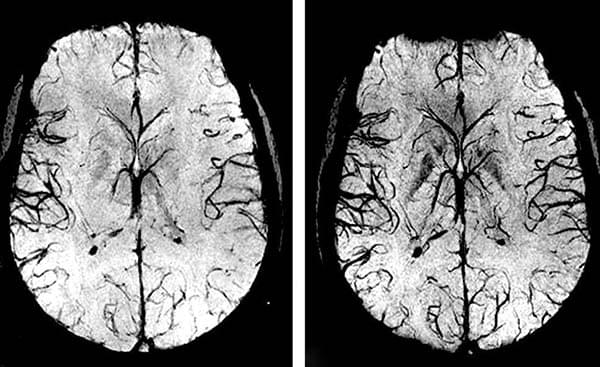

• Zerebrovaskuläre Erkrankungen. Es handelt sich um eine Unterbrechung der Blutgefäße im Gehirn, die zu einer mangelnden Versorgung der Gehirnzellen und damit zu einer Schädigung der Gehirnsubstanz führt. Dies führt häufig zu einem Schlaganfall, der zum Tod oder zu Behinderungen führt.

Wenn die Blutgefäße des Herzens (Koronararterien) durch Cholesterinablagerungen verstopft sind, verursacht dies zunächst Angina pectoris, kann dann aber zu einem Herzinfarkt führen. Und Blutgefäße, die an Kapazität verloren haben und das Gehirn nicht mehr richtig mit Blut versorgen, sind ein sicherer Weg zum Schlaganfall.

Die Blutzirkulation wird systemisch wieder hergestellt - in allen Gefäßen, Arterien und Kapillaren.